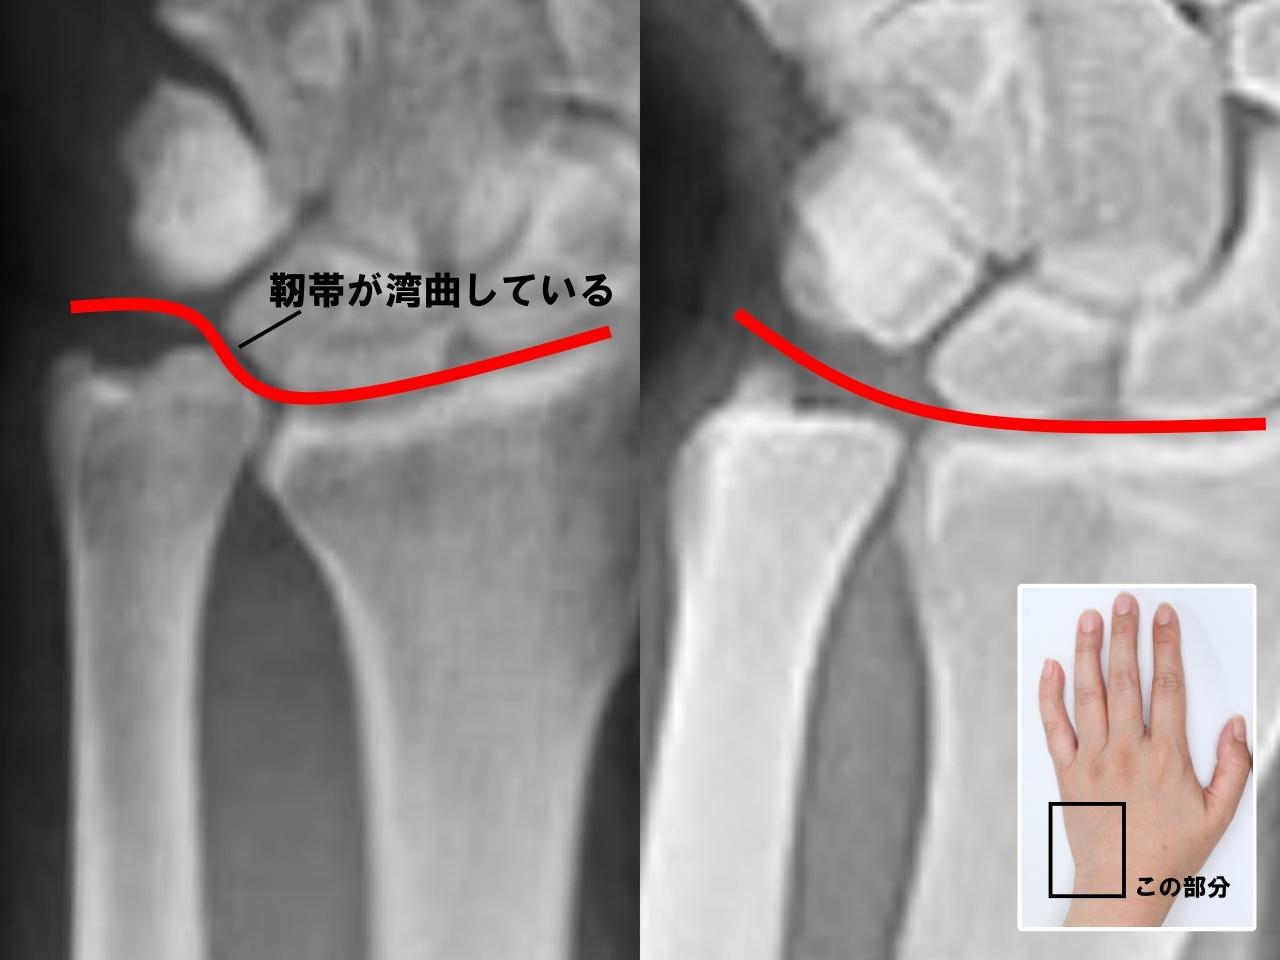

左手首のレントゲンの比較

TFCC損傷の左手首(画像左)、正常な左手首(画像右)

具体的に、手首の小指側にある軟骨と靭帯の3つの複合体で、小指側にある尺骨と呼ばれる突起した骨の脇のくぼみ辺りにあります。ゴルフやテニスなどの手を使うスポーツ、重たいものを運んだりする重労働や私生活などで、手首を繰り返し酷使した場合に小指側にある尺骨が突き上がってしまうことがあり、その際に小指側の複合体から手首を横切る靭帯の一つが突き上がった尺骨の上をゆがみながら横切ることになり、靭帯が緩んでしまう状態を『TFCC損傷』といいます」